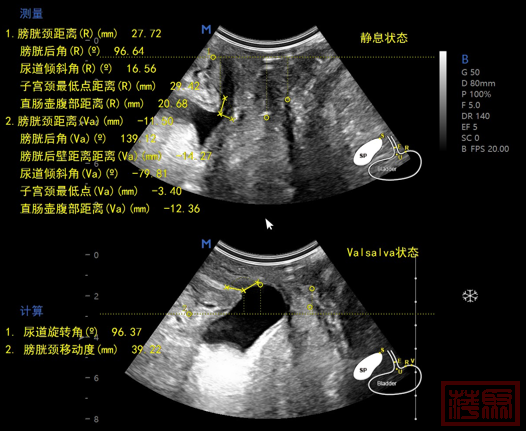

我科新引进盆底AI检查设备。盆底AI检查,就是通过超声波在人体组织中的传播和反射,用于评估组织的结构和功能。它是一种无创、无痛、无辐射的检查方法!利用超声的发射原理,穿透软组织并显示其内部结构,观察盆底组织器官结构和功能,

盆底AI检查针对盆底疾病,做到对患者全盆腔,实现全动态、实时扫描。做到自动扫描、自动测量。它可以迅速明确患者盆底支持结构出现的缺陷、损伤,并进一步判明功能障碍、病症的发生的根本原因。

这样既能够清晰、明白的解释清楚病因,也能为采取适当治疗方法,提供有效支撑。